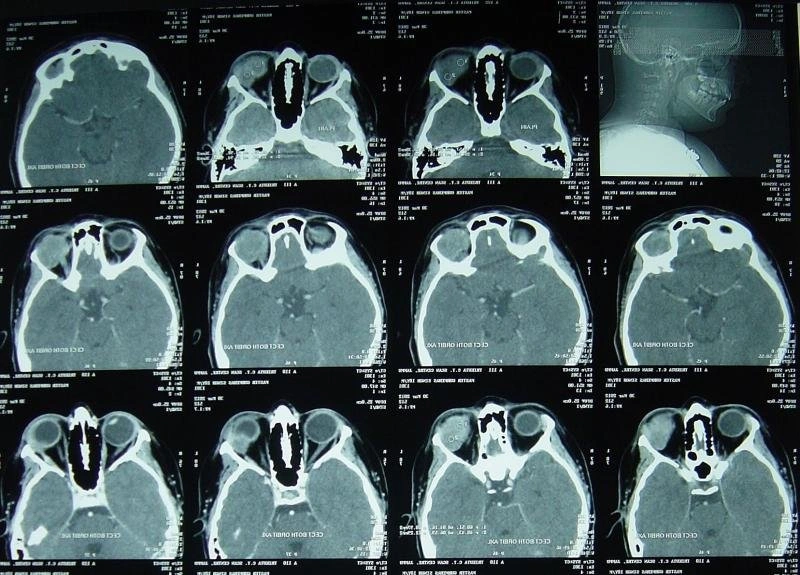

МРТ исследование "глазные орбиты и зрительные нервы"

Магнитно-резонансная томография глазных орбит и зрительных нервов  Проводится для определения стратегии лечения и объем   оперативного  вмешательства.  Позволяет   выявить новообразования,   воспаления,   последствия травмы.

В каких случаях требуется:  МРТ  зрительных  нервов  и  орбит проводят при подозрении на опухоль зрительного  нерва  или мягких тканей, поражение   зрительного нерва при рассеянном склерозе, при грыже мозга, одностороннем   экзофтальме   (пучеглазии), а   также при  перенесенных  травмах, резком  ухудшении зрения и т.д. Исследование, как правило, проводят по назначению врача.